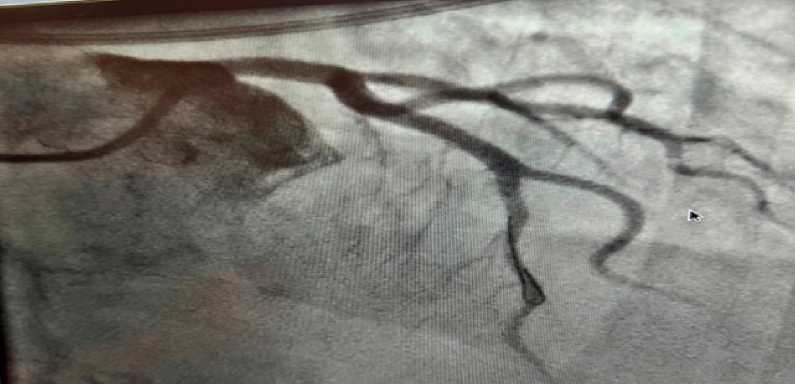

При выполнении КАГ определялась диссекция ствола левой коронарной артерии (ЛКА), привед-

Рис. 2. Коронароангиография: диссекция, окклюзия левой коронарной артерии. Fig. 2. Coronary angiography showing dissection with occlusion of the left main coronary artery.

шая к полной окклюзии сосуда без гемодинамически значимого атеросклероза в других коронарных артериях (рис. 2).